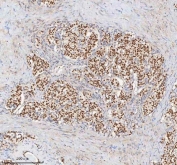

IHC staining of FFPE human urothelial carcinoma tissue with MACROH2A1 antibody. HIER: boil tissue sections in pH8 EDTA for 20 min and allow to cool before testing.